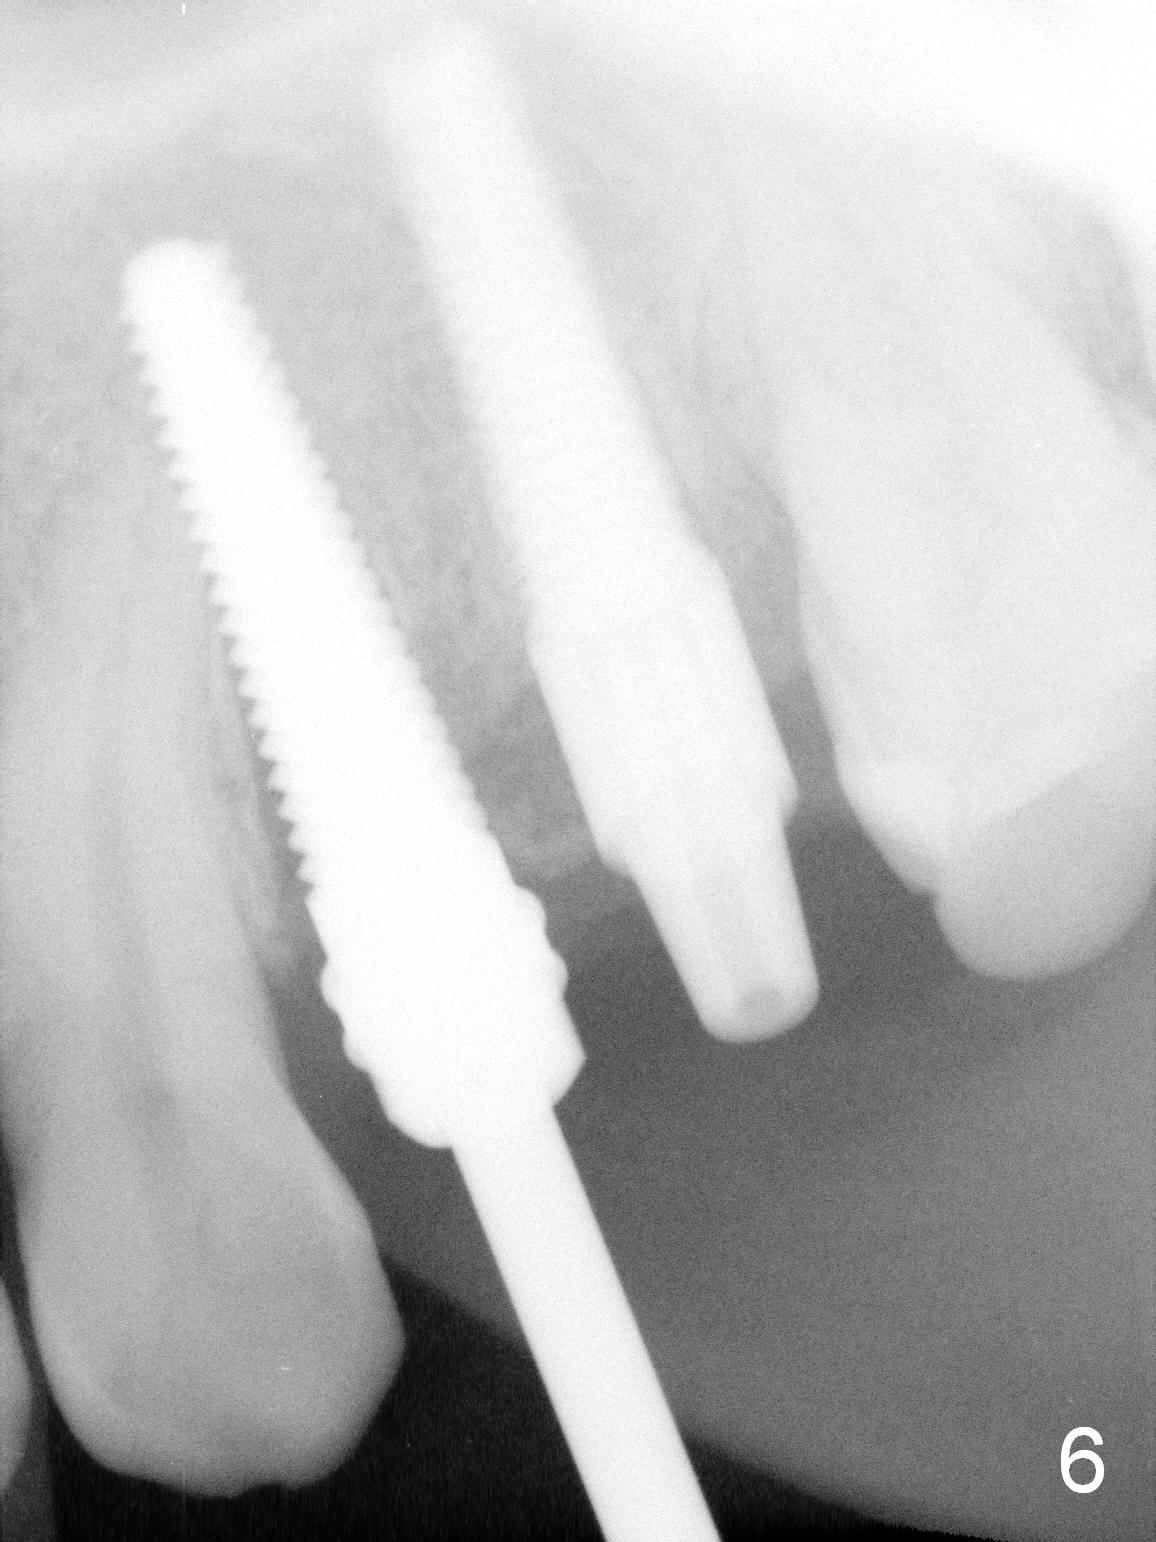

Taking 2 additional PAs with sensor 1 is frustrating (Fig.1,2), no apices shown. Osteotomy is done smoothly with 2 mm pilot drill at 20 mm, 2.5 mm reamer at 17 mm, and 3 mm reamer at 14 mm and 4.5x20 mm tap at 17 mm. The 1st intraop PA is taken with sensor 1 when 2 of 4.5x20 mm implants are placed (Fig.3); the implant at #12 is close to the root of the tooth #11. The 2nd PA is taken with sensor 2: the apex of #11 touches the implant at #12 (Fig.4). There is no separation when panoramic X-ray is taken (Fig.5). Effort is exerted to re-direct the osteotomy twice (Fig.6: tap; Fig.7: implant) without success. When the implant is removed, a PA is taken; it appears that the root of the tooth #11 has no damage (Fig.8). To obtain the best recovery, socket preservation is carried out with 50/50 cortical/cancellous allograft mixed with Osteogen (Fig.12 *) and Collagen Dressing (Fig.9: #12). A 2 (or 3)-unit provisional bridge (Fig.10: #12,13) is fabricated over the implant (Fig.9 I)/abutment (A) to cover these 2 sockets. After acid etching #11 D surface (Fig.9 >) and relining (Fig.11 *), the provisional bridge is bonded to the tooth #11 (Fig.11,12 black >) so that bone graft will be less likely dislodged.